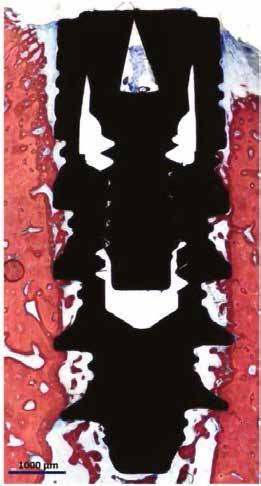

A maradó fogak gyökérreszorpciója patológiás folyamat. Az elváltozások elhelyezkedése alapján csoportosíthatjuk őket külső és belső reszorpciós folyamatokra. A külső gyökérreszorpciók egyre gyakrabban diagnosztizált formája a külső nyaki reszorpció (angolul External Cervical Resorption, ECR) [1. és 2. kép]. Az ECR egy komplex elváltozás, amely egyszerre érintheti a fog keményszöveti állományát, a parodontális szöveteket és előrehaladott esetben a pulpaszövetet is. A modern diagnosztikai eszközöknek köszönhetően egyre gyakrabban és egyre korábban kerül diagnosztizálásra ez a típusú lézió, így a kezelése is egyre inkább a mindennapi klinikum részévé válik az endodonciával foglalkozó kollégák számára. A 3 dimenziós diagnosztikai eszközök terjedésével felmerült az igény egy 3 dimenziós klasszifikációra. Patel és munkatársai 2018-ban kidolgoztak egy új klasszifikációt, amely segít az elváltozások kategorizálásában és a kezelések tervezésében [1]. A téma aktualitását jól mutatja, hogy ezzel egy időben az ESE (European Society of Endodontology) is kidolgozott egy állásfoglalást a külső nyaki reszorpciók diagnosztikájával és terápiás lehetőségeivel kapcsolatban [2].

Ötvenes éveiben járó páciensünk rutinellenőrzésre érkezett rendelőnkbe. A vizsgálat során felfigyeltünk a jobb felső metszőfogán kialakult, íny alatti elváltozásra. A röntgenfelvételen jól látható a kis méretű (Patel 1Ad) reszorpciós elváltozás [3. kép]

A megfelelő vizuális kontroll és az izolálhatóság kedvéért lebenyt alakítottunk [4. kép]. Így az abszolút izolálás már kivitelezhető volt és kofferdám izolálásban kezeltük a léziót [5. kép]. Mivel az elváltozás nem látható területen helyezkedett el, illetve a kavitás kis kiterjedését figyelembe véve kalcium-szilikát bázisú anyagot választottunk a restauráláshoz (Biodentine, Septodont) [6. kép]. Miután letelt a választott anyagunk kötési ideje (12 perc), zártuk a lebenyt [6. kép]. Páciensünk azóta is panaszmentes, kétéves kontrollon állapota rendben volt [7. és 8. kép].

Ötvenes éveiben járó hölgyet fogorvosa irányította hozzánk a bal alsó 4-es fogának nagy méretű reszorpciójával [9. kép]. A hölgy ragaszkodott foga megmentéséhez, így a kezelés megtervezéséhez CBCT felvételt készítettünk a fogról [10. kép]. A felvételen a Patel-féle klasszifikáció szerinti Patel 3Ap reszorpciós elváltozás látható. A szájüregi vizsgálat során a fog bukkális felszínén gyulladt ínyt, mély parodontális tasakot és a fog nyaki részén, a foganyagon átsejlő reszorpciós lacunát találtunk [11. kép]. A fog szenzibilitás vizsgálat során nem reagált hideg ingerlésre. A pulpális érintettség miatt elvégeztük a fog trepanálását, majd lebenyt alakítottunk a kavitás láthatóvá tételéhez [12.

1. és 2. kép: Külső nyaki reszorpciós elváltozások CBCT képen.9. kép: Referáló orvos által készített röntgenfelvétel – 10. kép: CBCT felvételen 3 dimenzióban értékelhető a reszorpciós kavitás kiterjedése.

11. kép: Kiindulási állapot.

12. kép: Trepanálás és lebenyalakítás. – 13. kép: A gyulladásos szövet eltávolítása után a kavitás kiterjedése jól láthatóvá vált.

14. kép: Kofferdam izolálás és a gyökércsatorna kiblokkolása guttapercha segítségével.

15. kép: A fog restaurálására mikro-hibrid kompozit tömőanyagot alkalmaztunk.

16. és 17. kép: Lebenyzárást követően befejeztük a fog gyökérkezelését. – 18. kép: 2 hónapos kontrollon a fog és az íny állapota is rendben.

kép]. Az üregben nagy mennyiségű gyulladásos szövetet találtunk, mely eltávolítása után láthatóvá vált a kavitás kiterjedése [13. kép]. A kisőrlő fogakra jellemző tengelyirányú, valamint oldalirányú terhelés kombinációja, valamint a je-

lentős foganyagveszteség miatt szerettük volna a lehető legjobban megerősíteni a fogat. A terület kofferdám gumilepedővel történő abszolút izolálása után a gyökércsatornát egy guttapercha segítségével kiblokkoltuk, ezzel megelőzve

a csatorna obliterálódását [14. kép]. Ezután megfelelő adhezív előkezelést követően kompozit tömőanyaggal restauráltuk az elváltozást (Essentia Universal, GC Europe) [15. kép]. Finírozást és alapos polírozást követően zártuk lebenyünket, majd újabb kofferdám izolálásban elvégeztük a fog gyökérkezelését [16. és 17. kép]. A kezelést követően páciensünk teljesen panaszmentes volt. Két hónapos kontrollon a fog teljesen ép, az íny tökéletes kitapadását tapasztaltuk [18. és 19. kép] Szondázási mélység a bukkális oldalon mindenhol 2 mm alatt volt.